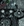

Central Vein Sign. The central vein sign (CVS) appears as a line or dot (depending on the MRI plane) that courses centrally through a lesion on susceptibility-weighted sequences.6,12 The CVS is the radiologic correlate to histologic perivenular inflammation in an MS plaque, and its identification on an MRI scan can help differentiate MS lesions from those resulting from other conditions, such as vascular disease or migraine.6 The CVS can be applied for MS diagnosis if at least 6 lesions have CVS positivity; if <10 lesions are present, CVS-positive lesions must outnumber CVS-negative lesions.6 This method is called “Select-6.” CVS positivity is not necessary to make a diagnosis of MS, but may aid the diagnosis in certain cases. The CVS was found in 73% of lesions in people with MS, showing 95% sensitivity and 92% specificity.8 This results in diagnostic accuracy with 90% sensitivity and 89% specificity when using Select-6 as a diagnostic tool.8 Examples of the CVS are shown in Figure 1.

Figure 1. Examples of classic MRI findings in multiple sclerosis. Central vein sign on fluid-attenuated inversion recovery MRI19,20 (A, B). Paramagnetic rim lesion on phase susceptibility MRI; reprinted from Hemond et al. Paramagnetic rim lesions are highly specific for multiple sclerosis in real-world data. Brain Commun. 2025;7(3), by permission of Oxford University Press (C).21 Left optic nerve signal hyperintensity on T2-weighted MRI sequence22 (D). Right cerebellar peduncle demyelinating lesion22 (E). Periventricular Dawson fingers on sagittal fluid-attenuated inversion recovery MRI sequence22 (F). Juxtacortical demyelinating lesions22 (G, H).

Paramagnetic Rim Lesions. Paramagnetic rim lesions (PRLs), which represent chronically active MS lesions, are characterized by an inflammatory rim of iron-laden microglia surrounding an inactive core. PRLs are specific MS markers and are not often found in MS radiologic mimics.6 PRLs are associated with high specificity (≥95%) for MS across numerous studies.6-8 PRLs also yield prognostic significance, with studies showing that the presence of ≥4 PRLs is associated with greater neurologic disability.6-8 PRLs appear as a hypointense (dark) rim on MRI susceptibility sequences, surrounding a correlating hyperintense lesion on T2/fluid-attenuated inversion recovery sequences. An example of a PRL is shown in Figure 1.

The 2017 McDonald criteria were not validated for use in individuals who were asymptomatic or had nonspecific or prodromal presentations.14 Therefore, application of the criteria was limited to people with a classical demyelinating event. With the 2024 McDonald criteria updates, there is decreased emphasis on clinical presentation and increased emphasis on the use of MRI scans. Identifying classical lesions on MRI scans “is now the cornerstone of diagnosis.”6 MS can contribute to the development and accumulation of nonspecific lesions—particularly in the subcortical white matter—however, these cannot count toward fulfillment of DIS criteria. Examples of classical lesions that can satisfy DIS criteria are shown in Figure 1.

Beyond expanding the definition of DIS, the 2024 McDonald criteria also increase the role of MRI scans by incorporating the CVS and PRLs as MS markers. However, supporting evidence for the CVS is strongest in periventricular or subcortical lesions, and PRLs have been described primarily in periventricular lesions. Data on PRLs in other locations are limited, and there is little evidence regarding the proportion of lesions with the CVS in other locations.6